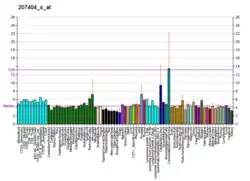

This receptor is unique among the serotonin receptors in that it is not known to be expressed by rats or mouse species, all of which lack the gene encoding the 5-HT1E receptor. However the genomes of the pig, rhesus monkey, and several lagomorphs (including rabbit) as well as the guinea pig each encode a homologous 5-HT1E receptor gene.[9] The guinea pig is the most likely candidate for future study of 5-HT1E receptor function in vivo. The expression of 5-HT1E receptors in the guinea pig brain has been pharmacologically confirmed; 5-HT1E receptor expression patterns of the human and guinea pig brains appear to be similar.[7] In the human cortex, the expression of 5-HT1E undergoes a marked transition during adolescence, in a way that is strongly correlated with the expression of 5-HT1B.[10]

Antagonists